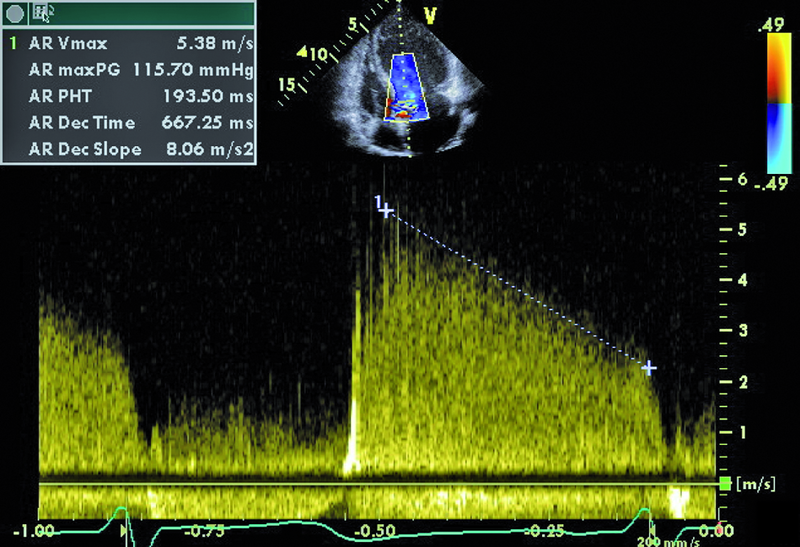

Infekcyjne zapalenie wsierdzia z zajęciem obu natywnych zastawek serca lewego nie budzi w tym przypadku wątpliwości. Proces zapalny może być rozpoznany echokardiograficznie na podstawie linijnych ech mogących odpowiadać rozerwanemu płatkowi zastawki aortalnej oraz na podstawie ciężkiego wypadania płatka zastawki mitralnej (flail), mającego zapewne charakter poinfekcyjny (ryc. 1). Stopień destrukcji zastawki mitralnej w porównaniu z zastawką aortalną wydaje się większy. Między segmentami A2 i P3 pojawia się tętniakowate uwypuklenie, będące pozostałością nacieczenia zapalnego i martwicy tkanki (ryc. 2). Tryb kolorowego doplera ujawnia dwa strumienie niedomykalności – jeden, ekscentryczny wynikający z wypadania przedniego płatka i biegnący wzdłuż bocznej ściany przedsionka (ryc. 3), i drugi pojawiający się w pewnej odległości od miejsca koaptacji, w miejscu, w którym fali zwrotnej trudno się spodziewać, jeśli struktura tkanki budującej płatek jest nienaruszona (ryc. 3, 4). Strumień niedomykalności mitralnej ma w tym wypadku charakter ostry i trafia do nieprzygotowanej i niepowiększonej jamy lewego przedsionka (ryc. 3, 4). Umiarkowana dotychczas niedomykalność aortalna, którą chory przez wiele lat dobrze tolerował, się nasiliła. Dowodem na to jest krótki czas spadku gradientu ciśnień aorta – lewa komora (poniżej 200 ms) (ryc. 5) oraz wyraźny sygnał wsteczny holodiastoliczny w aorcie zstępującej, świadczący o wysokiej wartości frakcji niedomykalności aortalnej (iloraz całki prędkości wypływu krwi na obwód i prędkości fali wstecznej 83%!) (ryc. 6).